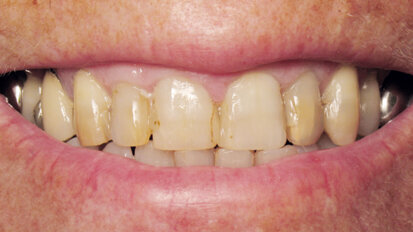

Nový úsměv za jeden den

Čt. 28. května 2020